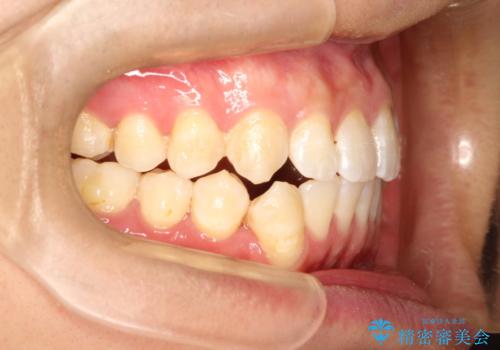

前歯がガタガタ インビザラインによる矯正

- 前歯がガタガタ、下の犬歯が飛び出ているのを主訴に来院されました。

下の奥歯を後方へ移動させてスペースを確保して、前歯を並べる計画としました。

目立たない装置をご希望されたので、インビザラインにて矯正治療を行いました。